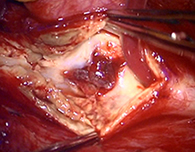

<実際の手術所見>

左前頭側頭開頭で動脈瘤クリッピング術を行った。

手術中は脳血管撮影装置を用いたHybrid手術を施行し、動脈瘤の消失を手術中に確認する。

手術中MEP(運動神経)VEP(視力)モニタリングで術後の視力低下や手足の麻痺を予防する。